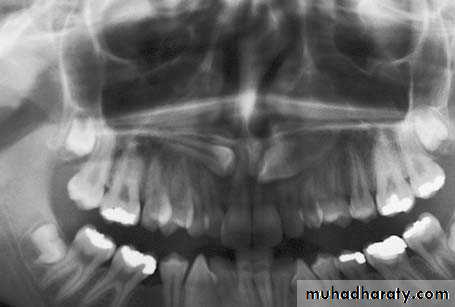

Radiograph showing impacted maxillary canines. Right canine is located labially while left canine is located palatally

Panoramic films

These are also used to localize impacted teeth in all three planes of space, as much the same as with two periapical films in the tube-shift method, with the understanding that the source of radiation comes from behind the patient; thus, the movements are reversed for position. *(image size distortion; object further away from the image receptor (film) will be depiceted more magnified than objects closer to the film